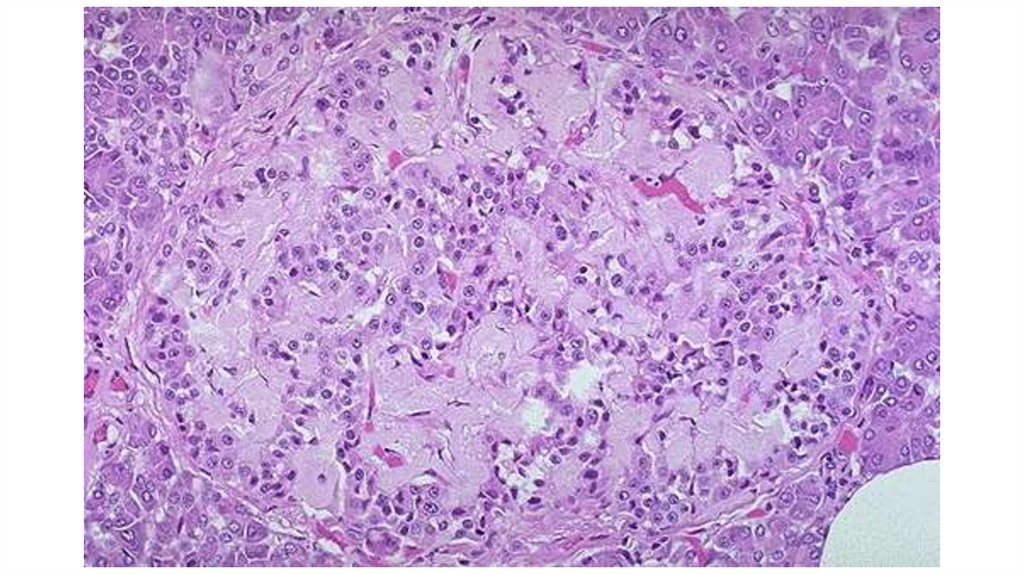

12. Меланома

13. Эндоцервикоз шейки матки